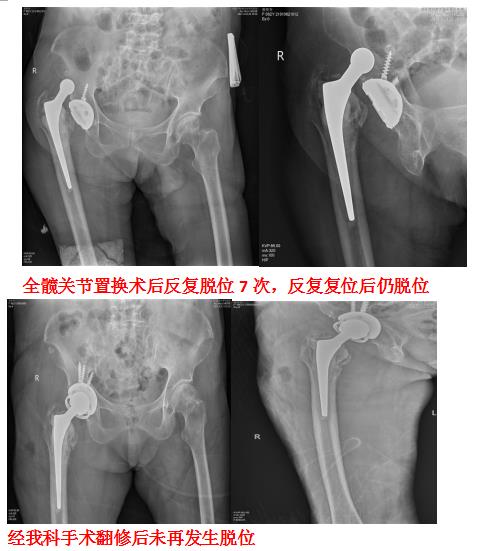

2、髋关节置换术后翻修: